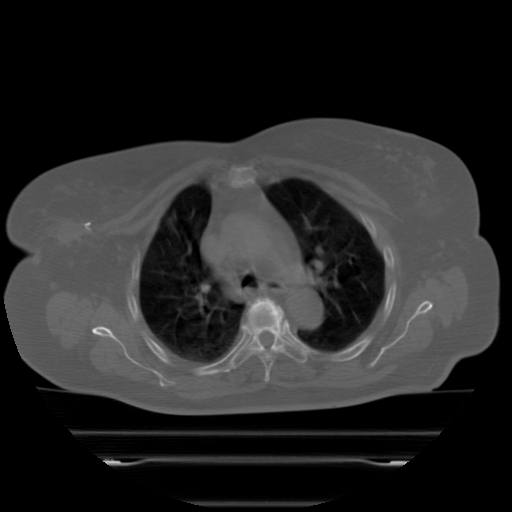

ClearRT® Images

Imaging Information

ClearRT®

Protocol

Thorax-medium-FoV50cm

Scan Length

30 cm

KVCT Imaging Time